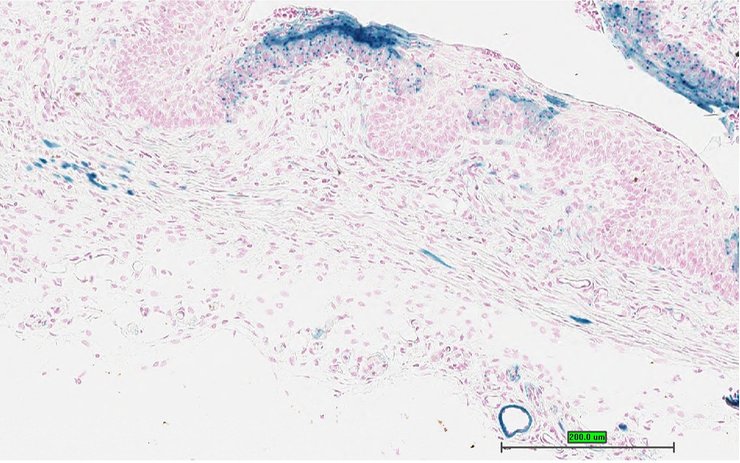

Specimen UC Davis_1850856: postnatal adult; Mid1ip1tm1.1(KOMP)Vlcg/Mid1ip1+ (more )

TS28: skin Present UC Davis_1850856

Specimen UC Davis_1850857: postnatal adult; Mid1ip1tm1.1(KOMP)Vlcg/Mid1ip1+ (more )

TS28: skin Present UC Davis_1850857

Specimen UC Davis_1850858: postnatal adult; Mid1ip1tm1.1(KOMP)Vlcg/Mid1ip1+ (more )

TS28: skin Present UC Davis_1850858